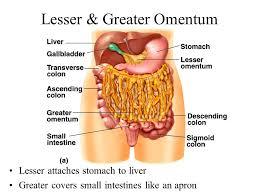

5

Lesser Omentum

6

Greater Omentum